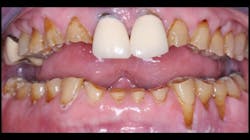

Previous periodontal disease. Early in the profession’s experience with implants, many thought that periodontal disease disappeared when the teeth were removed. That has since been disproved. Make sure you find out about previous periodontal disease in your patients before placing implants and proceed cautiously.

Oral hygiene. Most potential implant patients have lost their teeth due to many factors, but inadequate oral hygiene is one of the most common reasons. Their oral hygiene behavior is not likely to change, since they may believe their dental problems are over when implants are placed. Microbes present in periodontal disease are on the list as a potential reason for peri-implantitis and implant failure.

Improper implant placement. This is an extremely important factor. Placement of implants in locations where they receive abusive occlusion or excessive loading is inviting failure (figures 2–4).